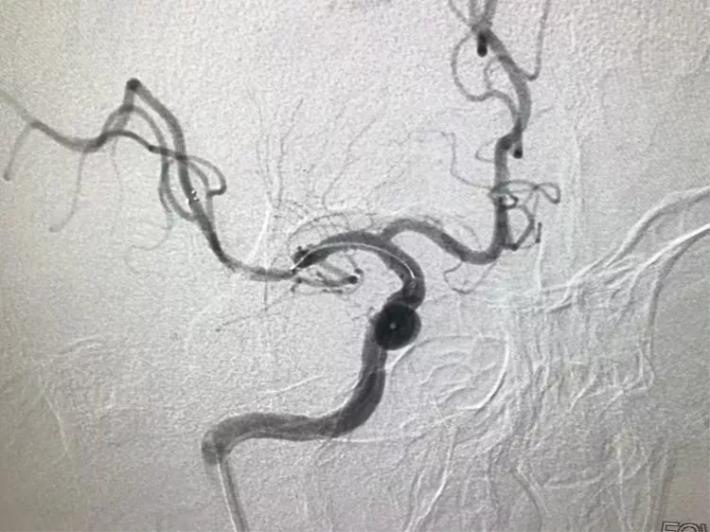

立即桥接取栓,造影显示:左侧颈内动脉闭塞。

右侧颈内动脉向左侧没有代偿。

椎动脉造影显示后交通动脉没有代偿。

微导管进入左侧大脑中动脉远端真腔。

置入支架。

可见大脑中动脉有血流。

取出支架未见血管开通。

再次置入微导管。

置入支架取栓。

见颈内动脉开通,大脑中动脉远端有血栓逃逸。